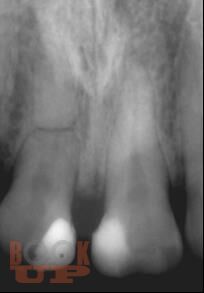

Представление материала сопровождается авторскими рисунками, фотографиями данными рентгенологических методов исследования, описанием клинических примеров.